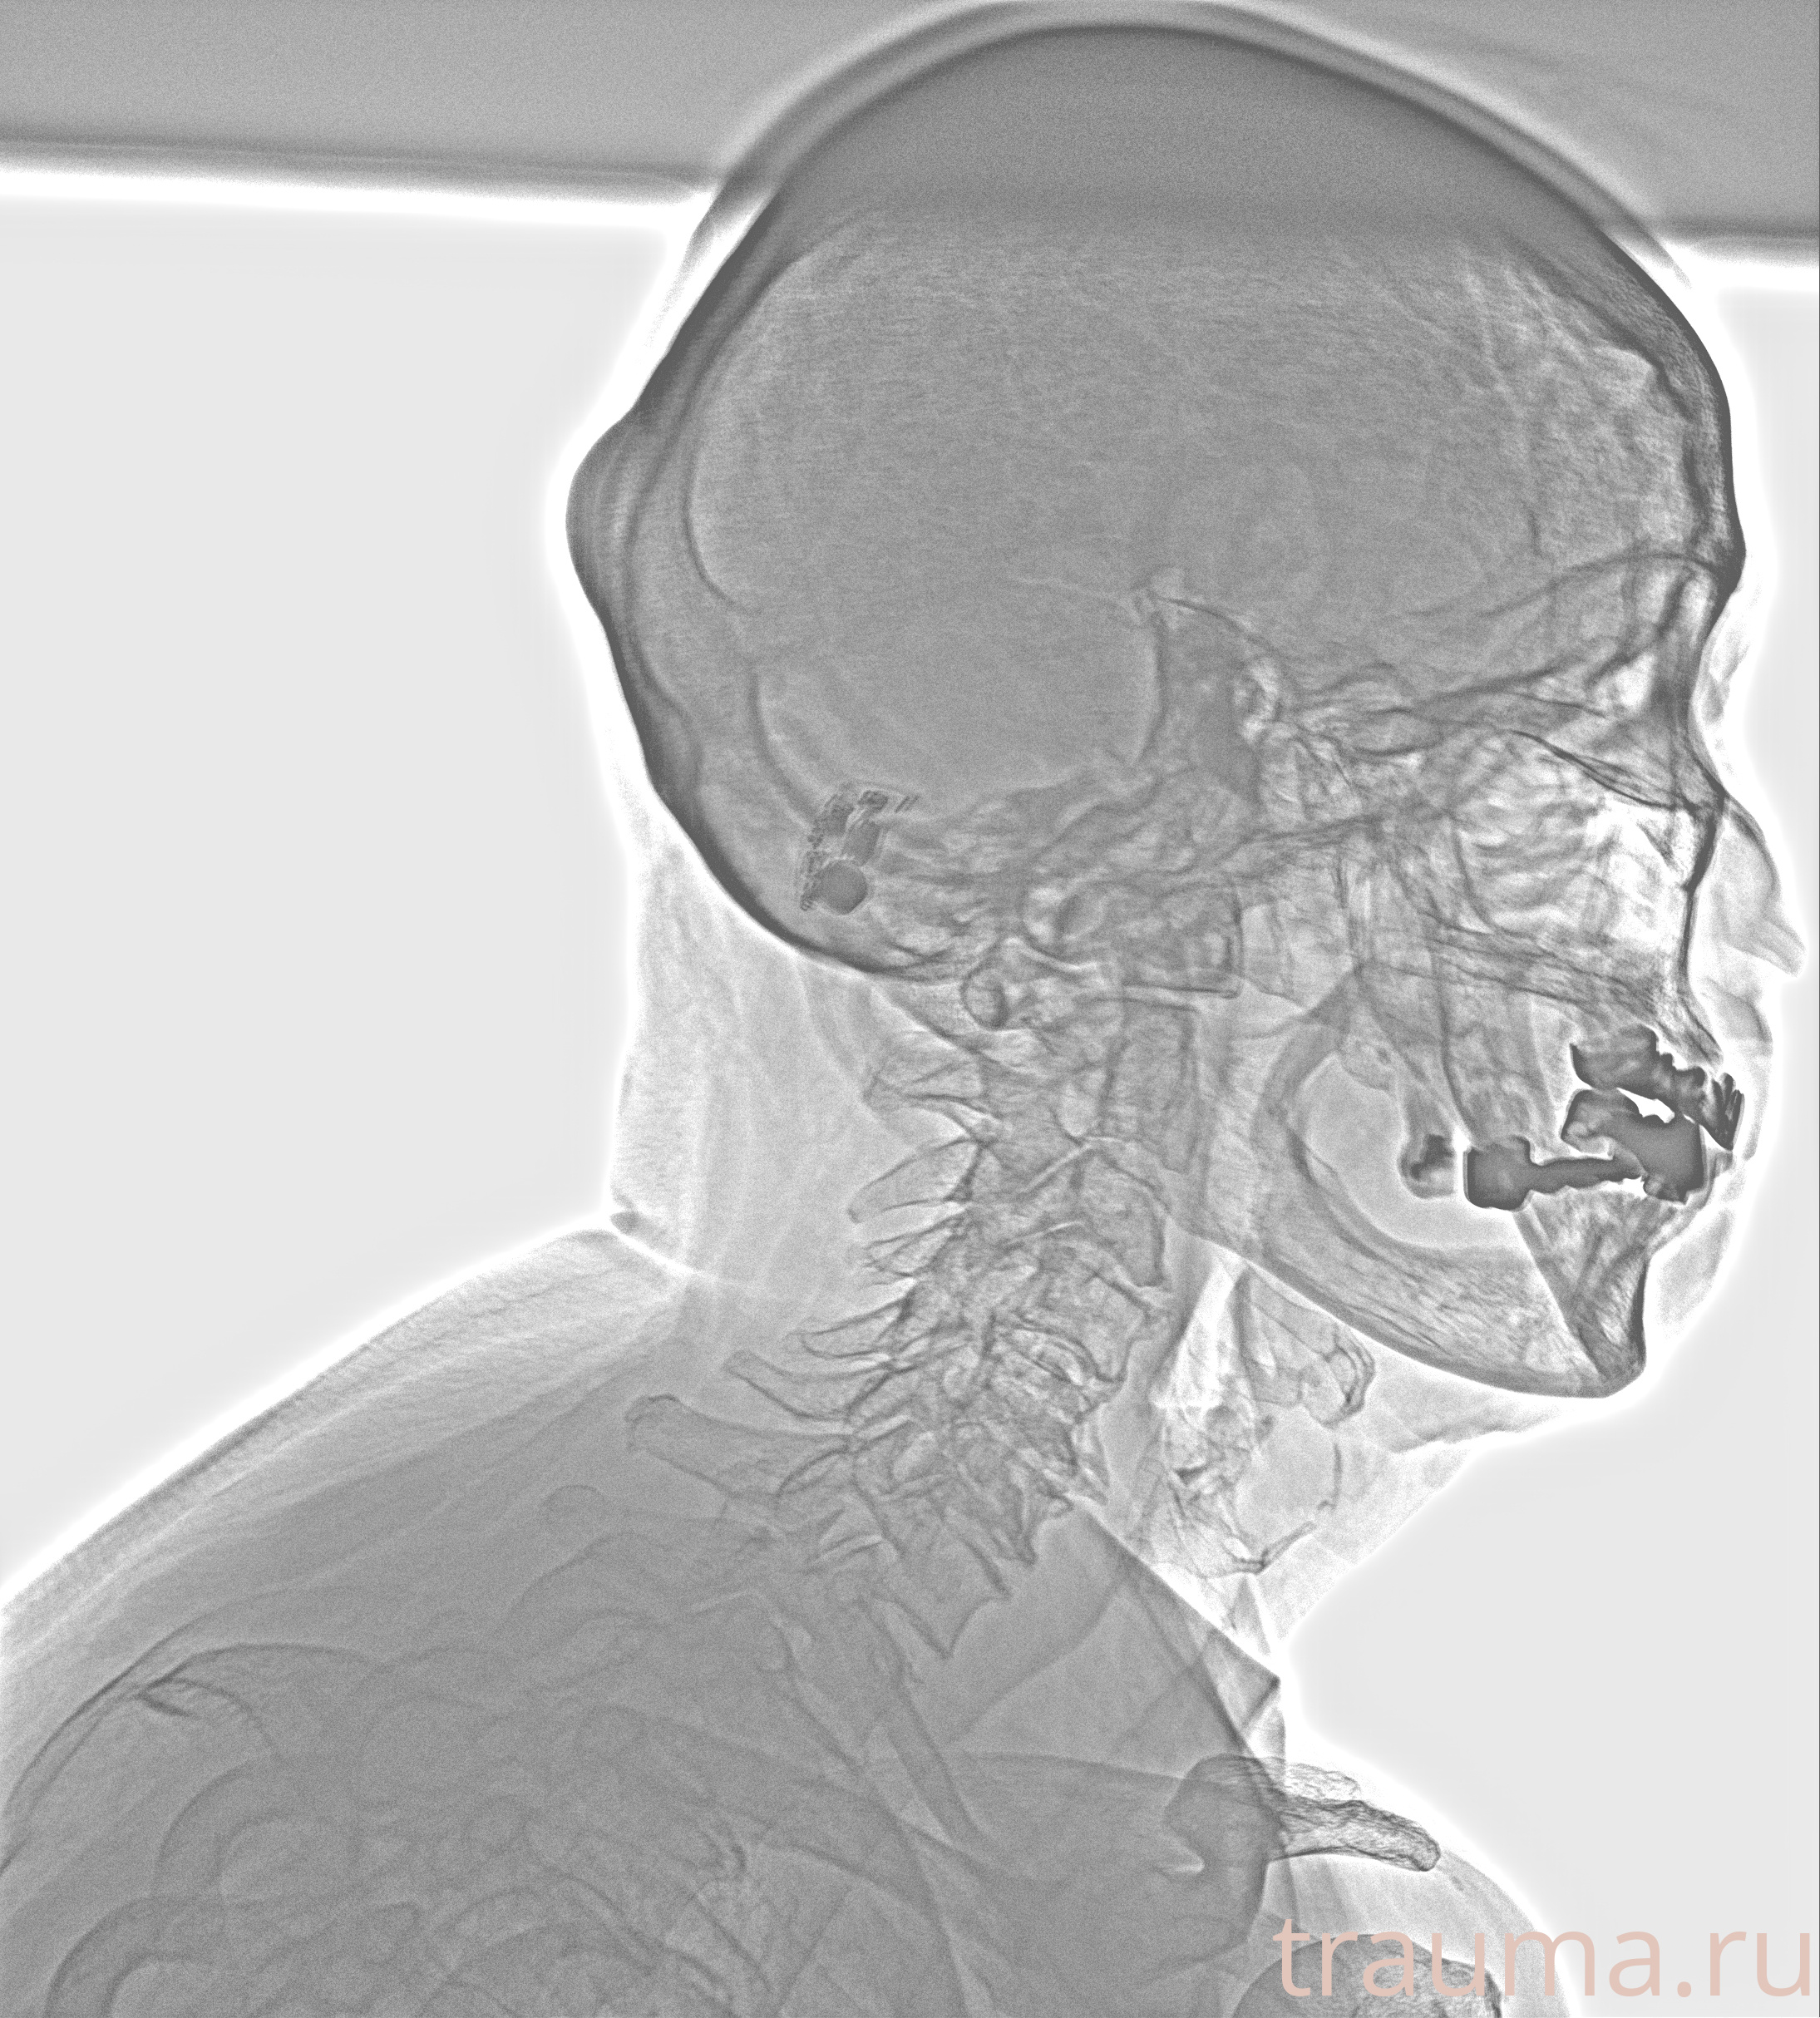

Рентгенограммы

Рентген на дому: по вашему адресу приезжает врач-рентгенолог, травматолог-ортопед с мобильным рентгеновским аппаратом, проводит диагностику травмы или заболевания, делает необходимые рентгенограммы, дает рекомендации по дальнейшему лечению. Получить качественные снимки в домашних условиях возможно благодаря уникальной методике, разработанной МосРентген Центром для института  Склифосовского